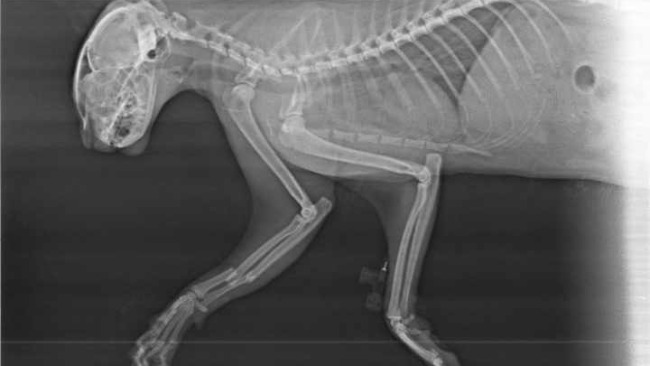

Cześć jestem właścicielem kota o małym rozumku, który chcąc się poopalać niestety przecenił swoje rozmiary i nie zmieścił się na parapecie co skończyło się wypadkiem. Pandzia spadła z trzeciego piętra lecz miała dużo szczęścia, bo skończyło się to na wybitym ząbku, stłuczeniach i złamanej łapie. Niestety łapka jest na tyle poważnie złamana, że potrzebna jest kosztowna operacja ortopedyczna. Ten niespodziewany wypadek i nagła wizyta w przychodni weterynaryjnej pochłonęła nasze oszczędności i nie mamy funduszy na operacje. Z tego powodu bardzo prosimy o Wasze wsparcie, bardzo nam zależy aby kot był w pełni sprawny i mógł się cieszyć beztroskim życiem, a bez operacji nie będzie to możliwe.